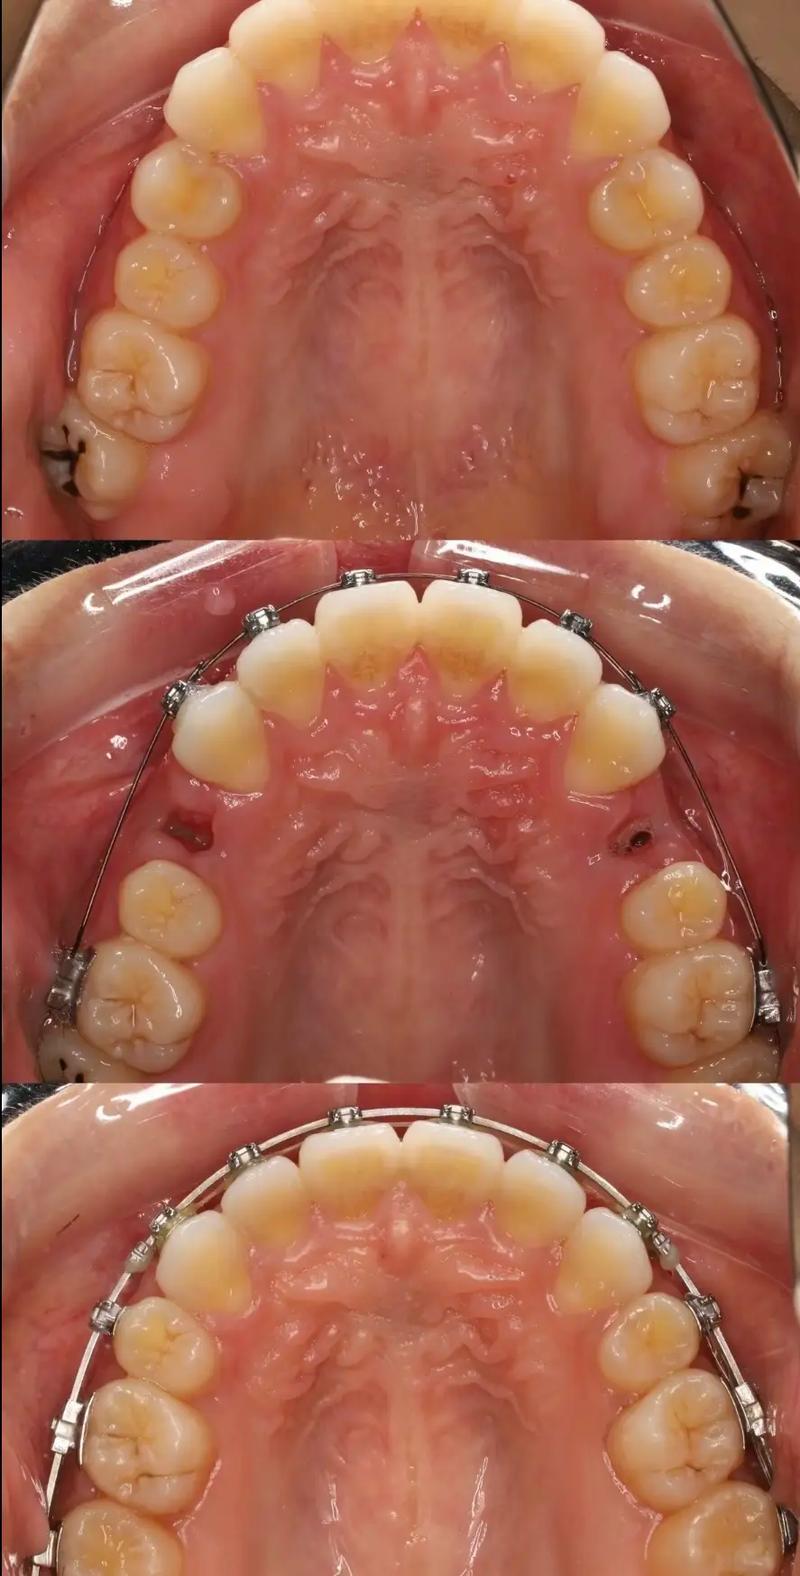

正畸片段弓的类型与临床应用场景

根据片段连接方式和功能,正畸片段弓可分为多种类型,不同类型适用于不同的牙齿问题,以下通过表格对比常见类型及其特点:

| 连续片段弓 | 多颗目标牙齿通过连续弓丝连接,力量分散 | 2-4颗前牙的拥挤排齐、间隙关闭 | 力量柔和,协同移动效率高,减少牙齿反复调整 |

| 非连续片段弓 | 目标牙齿弓丝独立,通过辅簧或弹性线连接 | 单颗牙齿压低/伸长、扭转纠正 | 精准控制单颗牙齿移动,避免邻牙干扰 |

| 复合片段弓 | 结合连续与非连续设计,联合使用辅件(如支抗钉) | 局部牙齿移动与整体咬合调整(如深覆合矫正) | 兼顾局部精准性与整体稳定性,适应复杂病例 |